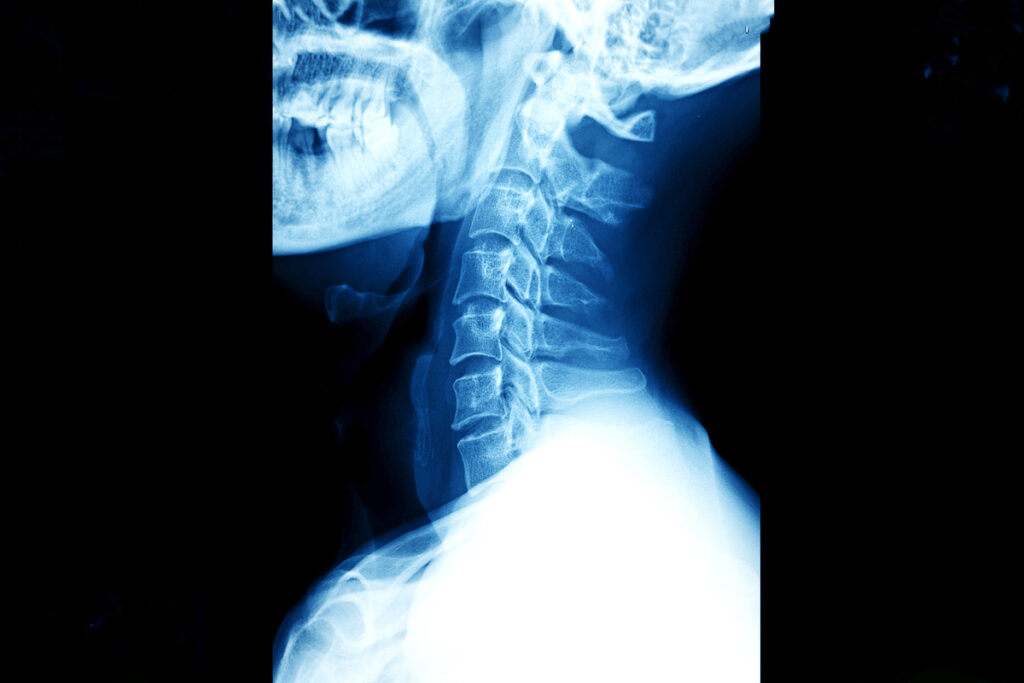

Шеннон Мэллой попала в серьёзную аварию, в которой произошло редчайшее явление — внутреннее обезглавливание. Её позвоночник полностью отделился от черепа, а все связки и сухожилия были разорваны. И всё же она выжила.

Шеннон перенесла несколько операций. Её череп зафиксировали к позвоночнику. Из-за повреждения нервов её глаза постоянно косили, а речь стала затруднённой. Переломы таза и лодыжки не могли быть сразу исправлены — врачи ждали, пока спадёт отёк мозга и спинного мозга.